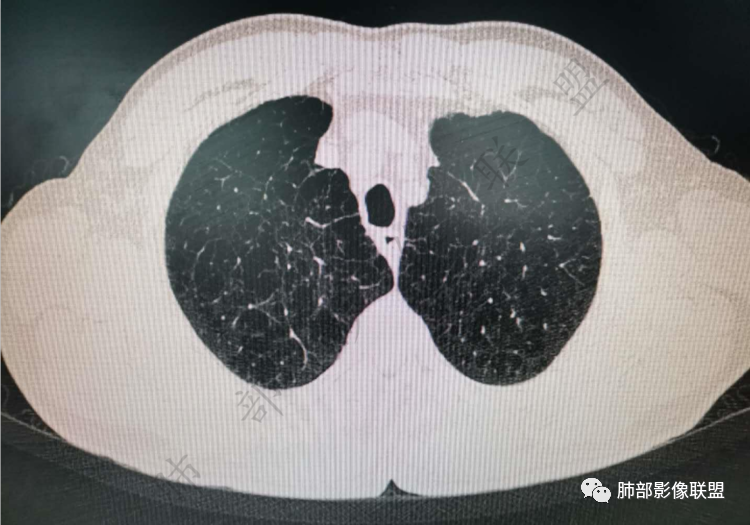

右肺上类圆形叶结节,周边见细软毛刺,增强后呈环形明显强化,内部坏死,邻近胸膜光滑,结合病史2个月明显增大,考虑炎性可能性大。

老年男性,炎性指标略高,肺气肿背景。右肺上叶胸膜下结节,部分边缘平直,部分稍模糊,软长毛刺,血管增粗,病灶中心密度减低,邻近脂肪间隙清晰。考虑炎性肉芽肿或慢性炎症,鉴别鳞癌。

老年男性,炎性指标略高,肺气肿背景。右肺上叶胸膜下结节,部分边缘平直,部分稍膨隆,供血血管增粗,增强扫描病灶中心密度减低,呈环形强化,邻近脂肪间隙清晰。考虑炎性肉芽肿或慢性炎症,鉴别鳞癌。

肺气肿背景

实性有隆起的小结节,内部有坏死、周围包括内乳动脉有增粗

病史提到有明显增大(现在看上去也不算太大,所以是不是明显增大存疑)

右肺上叶前段胸膜下结节,边缘分叶毛刺,血管集束,支气管截断,纵膈胸膜牵拉,内乳动脉增粗,密度不均,中央可见坏死,两个月短期随访结节有增大,考虑恶性,腺癌。鉴别结核。

肺气肿背景,右肺上叶纵隔旁胸膜下结节,有血管集束,支气管堵塞,内乳动脉增粗,增强不均匀强化,内可见低密度区。考虑为恶性可能性大

老年男性,肺气肿背景,右肺上叶胸膜下弧立实性不规则结节,密度不均,其内低密度坏死影,支气管似有截断,血管集束,2月复查明显增大,考虑恶性,鳞癌可能大,鉴别炎性肉芽肿

老年男性,炎性指标略高。影像表现右肺上叶胸膜下结节,膨胀性生长部分边缘平直,边界清晰,病灶可见血管集束征,近段支气管阻断?增强扫描病灶中心密度减低,低密度区边界模糊,外围环形强化。老年性,不能排除恶性病变,周围性鳞癌,其次才考虑炎性肉芽肿或慢性炎症

老年男性患者。肺气肿 ,轻微的支气管扩张,右肺上叶前段胸膜下小结节影,轻分叶,长短不一毛刺,边界欠光整,明显的强化。考虑腺癌或鳞癌。

右上叶前段结节,肺气肿背景,血管滋养丶支气管截断,与纵隔脂肪间隙清析

老年男性,肺气肿背景,右肺上叶前段胸膜下结节,部分边缘毛糙,血管集束增粗,支气管似有截断,胸膜牵拉,结节密度不均,两个月随访结节有增大,考虑恶性,肺癌可能;另右肺上叶后段肋胸膜区小片状类结节影,考虑炎性可能。

老年男性,有肺气肿,估计有吸烟。病灶靠近胸膜宽基底紧贴胸膜。有直边征,有U型凹陷,为良性征象,有血管集数征,小的支气管截断征,为恶性征象。病灶周围没有树芽征,似乎找不到卫星灶,没有葫芦兄弟,增强扫描病灶内有空泡,所以综合考虑恶性可能大,鳞癌和粘液腺癌鉴别。良性的话结核和隐球菌鉴别。

右肺上叶前段结节,边缘毛糙,血管进入,局部细支气管似闭塞,增强有强化,中心密度似减低,2月明显增大,肺气肿背景,首先考虑炎性结节,鳞癌增大可以很快,对比老片看看

右肺上叶前段胸膜下结节,近段支气管截断,血管伸入结节内,密度不均,同侧临近内乳动脉增粗,不均匀强化,肺气肿背景,两月明显增大,考虑低分化鳞癌,隐球菌代排

老年男性,肺气肿背景,右肺前上纵隔旁结节,边缘平直,密度均匀,伴长索条影,增强均匀轻中度强化,结合2个月结节明显增大,倍增时间短,腺癌不考虑,考虑炎性肉芽肿,鉴别炎性肌纤维母细胞瘤

老年男性,白细胞计数及CRP稍高,右肺上叶结节,两个月来有增大,部分边缘可见边界模糊的GGO,局部边缘平直、凹陷,临近胸膜增厚,内见坏死,坏死区边界未见明显壁结节,壁较厚而且均匀强化,支气管似乎有扩张然后截断,近端血管增粗明显。考虑炎性病变,脓肿?有结核病人密切接触史,注意是否为结核。有点难以理解的是为什么右侧内乳动脉增粗明显。

老年男性,无症状,炎性指标增高。肺气肿背景,右肺上叶前段结节,边缘部分平直部分澎隆,血管集束,支气管至病变边缘似截断,近端扩张。增强环形强化,中心坏死。两月内病灶增长太快,考虑炎性肉芽肿,慢性脓肿?结核?癌待排。

支气管变形、壁增厚,提示慢性支气管炎症

边缘平直

宽基底与胸膜相连,附近胸膜增厚,糊墙

内乳动脉关系似乎不密切

内部有低强化区,边界尚清

还是支持炎性放前面,恶性待排